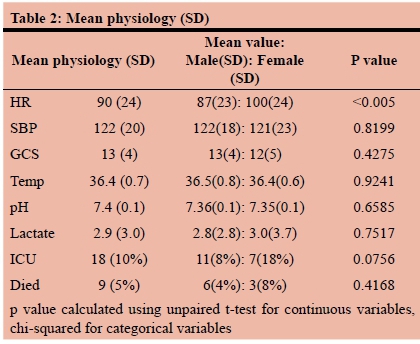

RESULTS: During the five-year study period, a total of 179 patients were included. The mean age was 29 years (SD12) and there were 139 (77%) males and 40 (23%) females. Of these, 16 had a previously established psychiatric diagnosis and two had a prior history of having sustained self-harm. The previously diagnosed psychiatric illnesses included mood dysphoria disorders (5), schizophrenia (3), substance abuse and dependency (1), anti-social personality disorder (1) and unspecified (6). The mechanism was penetrating trauma in 47 (26%). The penetrating mechanisms included stab wounds (SW) in 33, gunshot wounds (GSW) in 10, broken glass in 2 and a single impalement. Blunt mechanisms accounted for the remaining 131 (73%) injuries. The most common mechanism of blunt self-harm was hanging in 101 patients. This was followed by vehicular related trauma (8), jumping in front of a train (1) and jumping from a height (1). In 17 patients the exact mechanism of the blunt trauma was unclear. There was no statistical difference in the mechanism of injury between male and female patients. There were 38 (28%) men and 9 (23%) women who sustained a penetrating injury and there were 100 (72%) male and 31 (78%) female patients who had a blunt mechanism of injury. A total of 53 CT scans were obtained, 40 chest X-rays, 9 abdominal X-rays and 2 ultrasounds. There were 113 neck injuries, 68 head injuries, 24 abdominal injuries, 15 upper limb and 15 lower limb injuries and four facial injuries. A total of 32 operations were performed. These included laparotomy (14), neck exploration (5), tracheostomy (4). A total of 22 patients developed a complication

Demographics and presenting physiology

During the five-year study period, a total of 179 patients sustained self-harm and were managed by the PMTS. The mean age was 29 years (SD12) and there were 139 (77%) males and 40 (23%) females. Of these, 16 had a previously established psychiatric diagnosis and two had prior histories of having sustained self-harm. The previously diagnosed psychiatric illnesses included MDD (5), schizophrenia (3), substance abuse and dependency (1), anti-social personality disorder (1) and unspecified (6). In the patients who attempted to hang themselves, 60.9% had consumed alcohol just prior to the incident. There were 139 patients from the city of Pietermaritzburg and 40 from the rural areas of western KZN. Table 1 summarizes the demographics of the cohort. Table 2 summarizes the presenting physiology of the patient cohort.